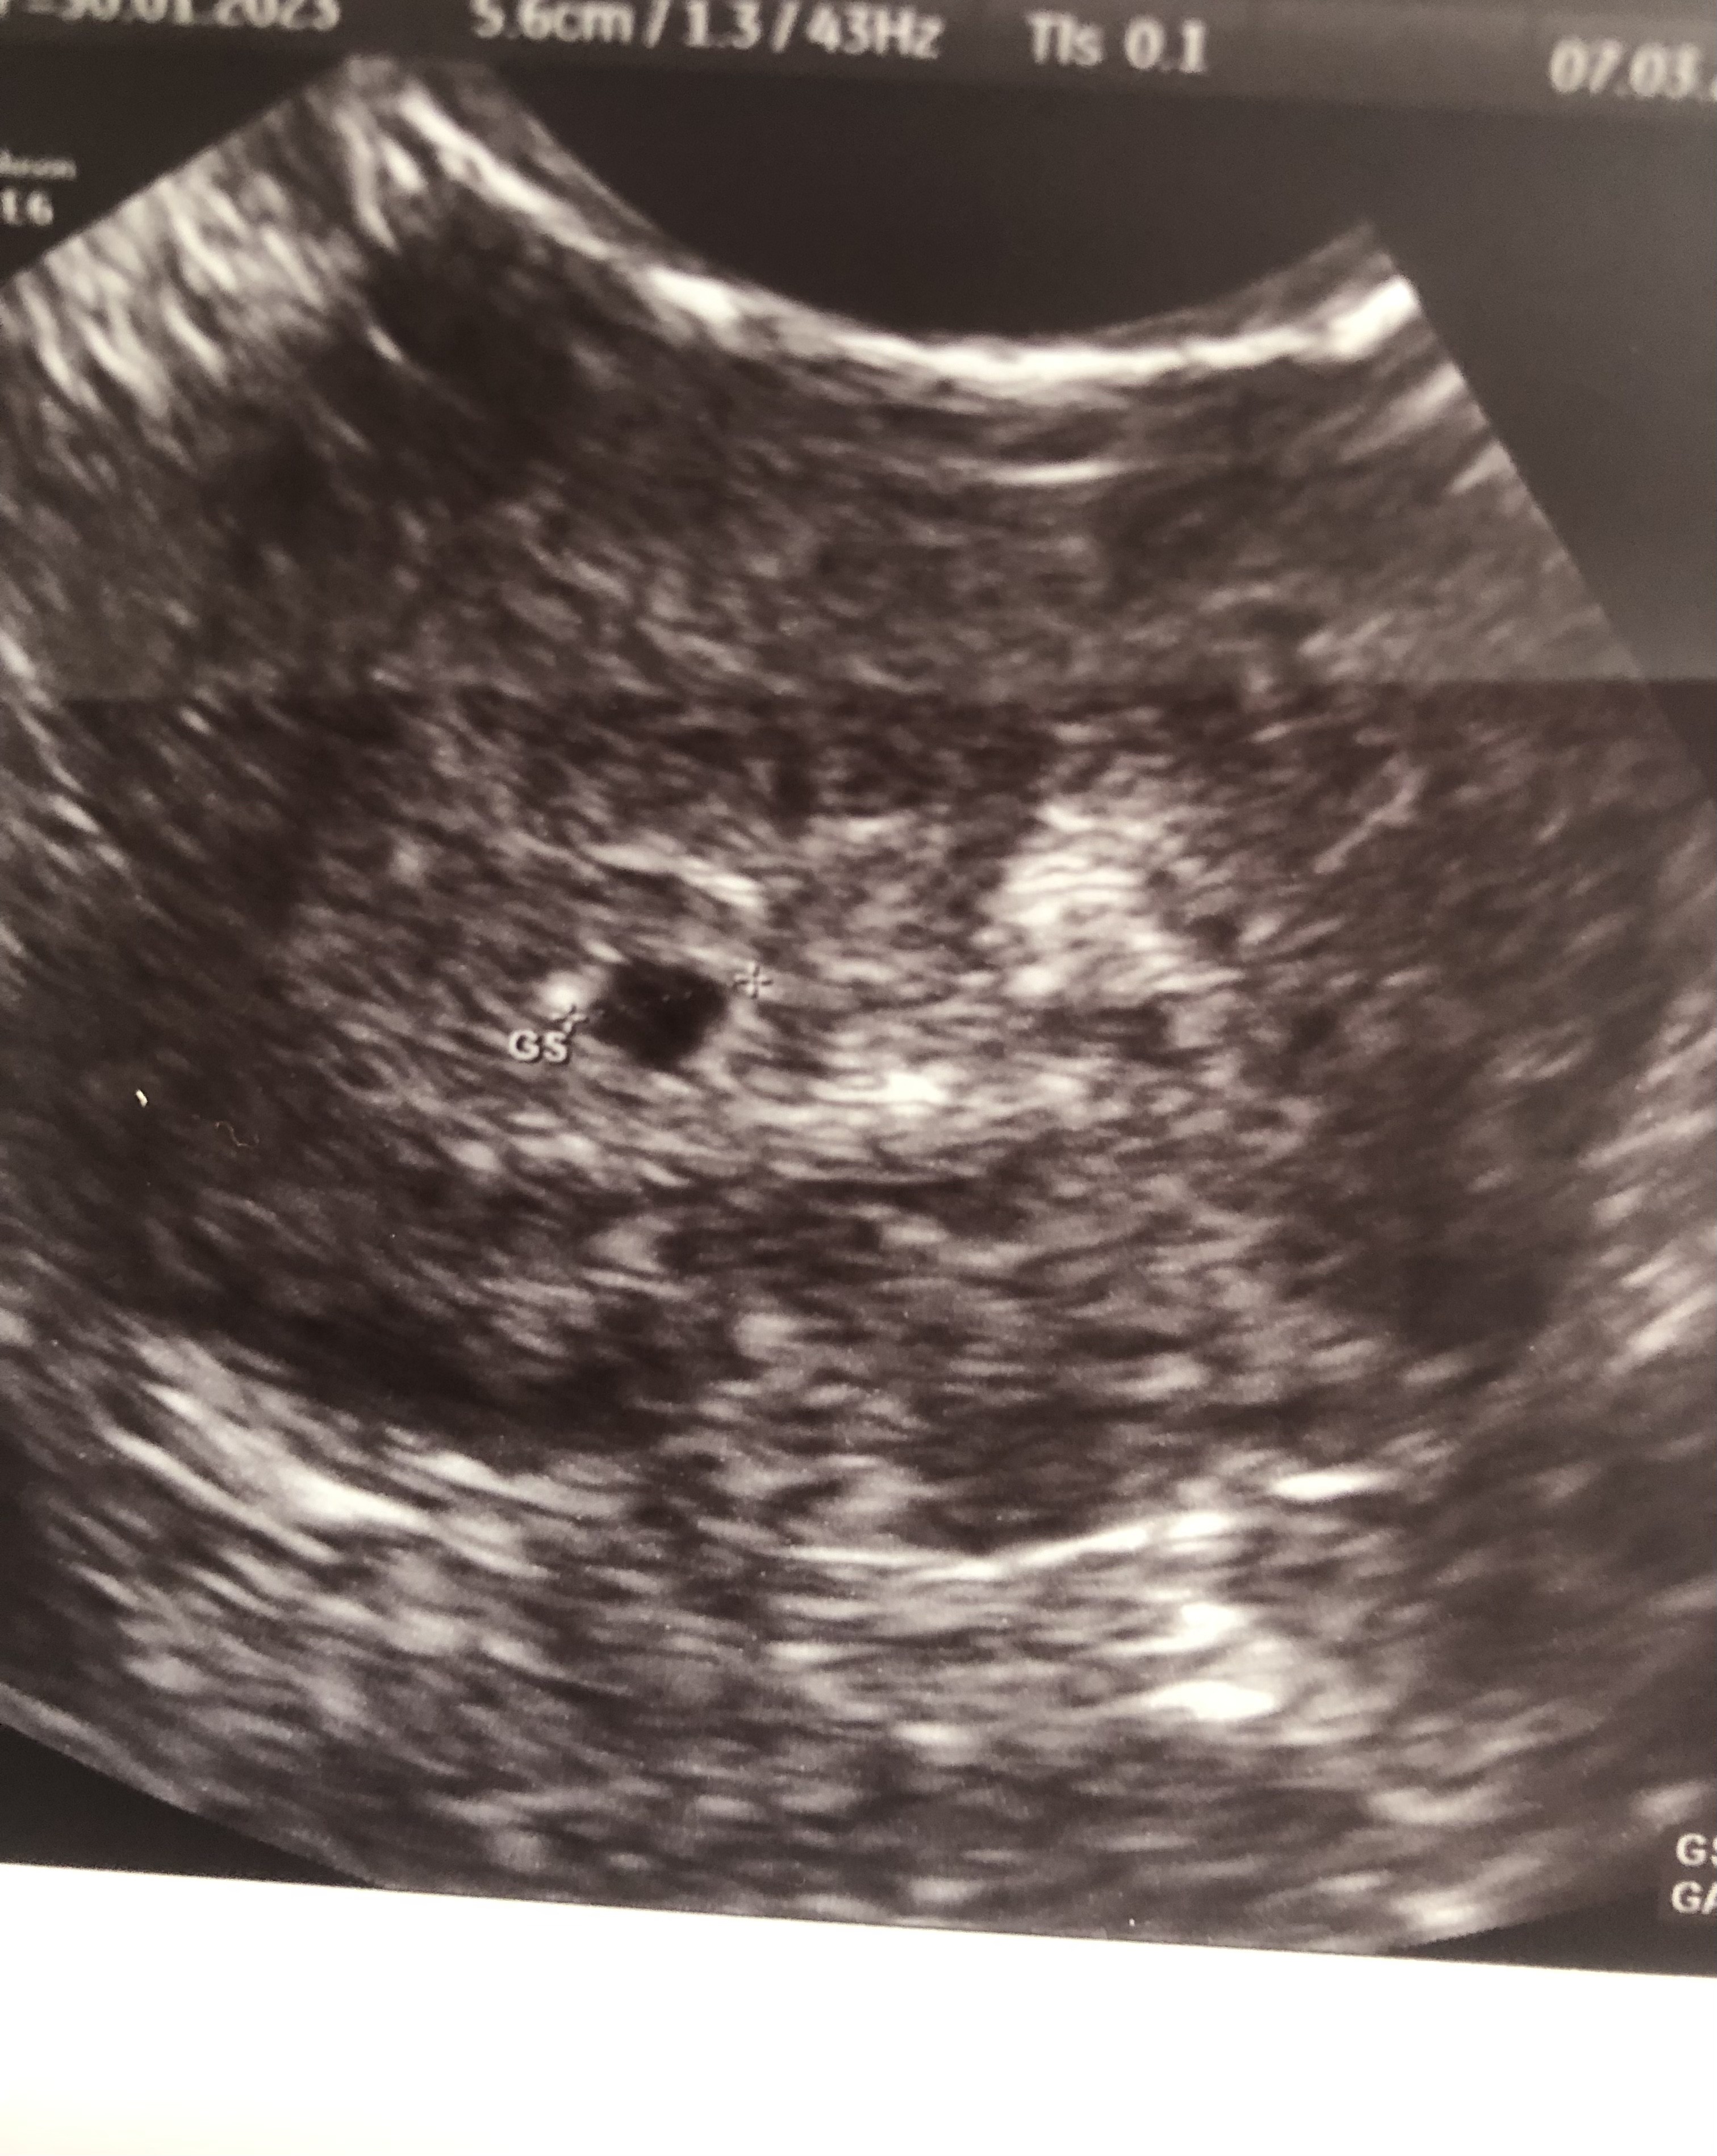

Byłam na pierwszej wizycie z USG w 5+1- wtedy był widoczny pęcherzyk ciążowy z pęcherzykiem żółtkowym.

Tak to wyglądało: ta biała kropka nad pęcherzykiem ciążowym to właśnie pęcherzyk żółtkowy.